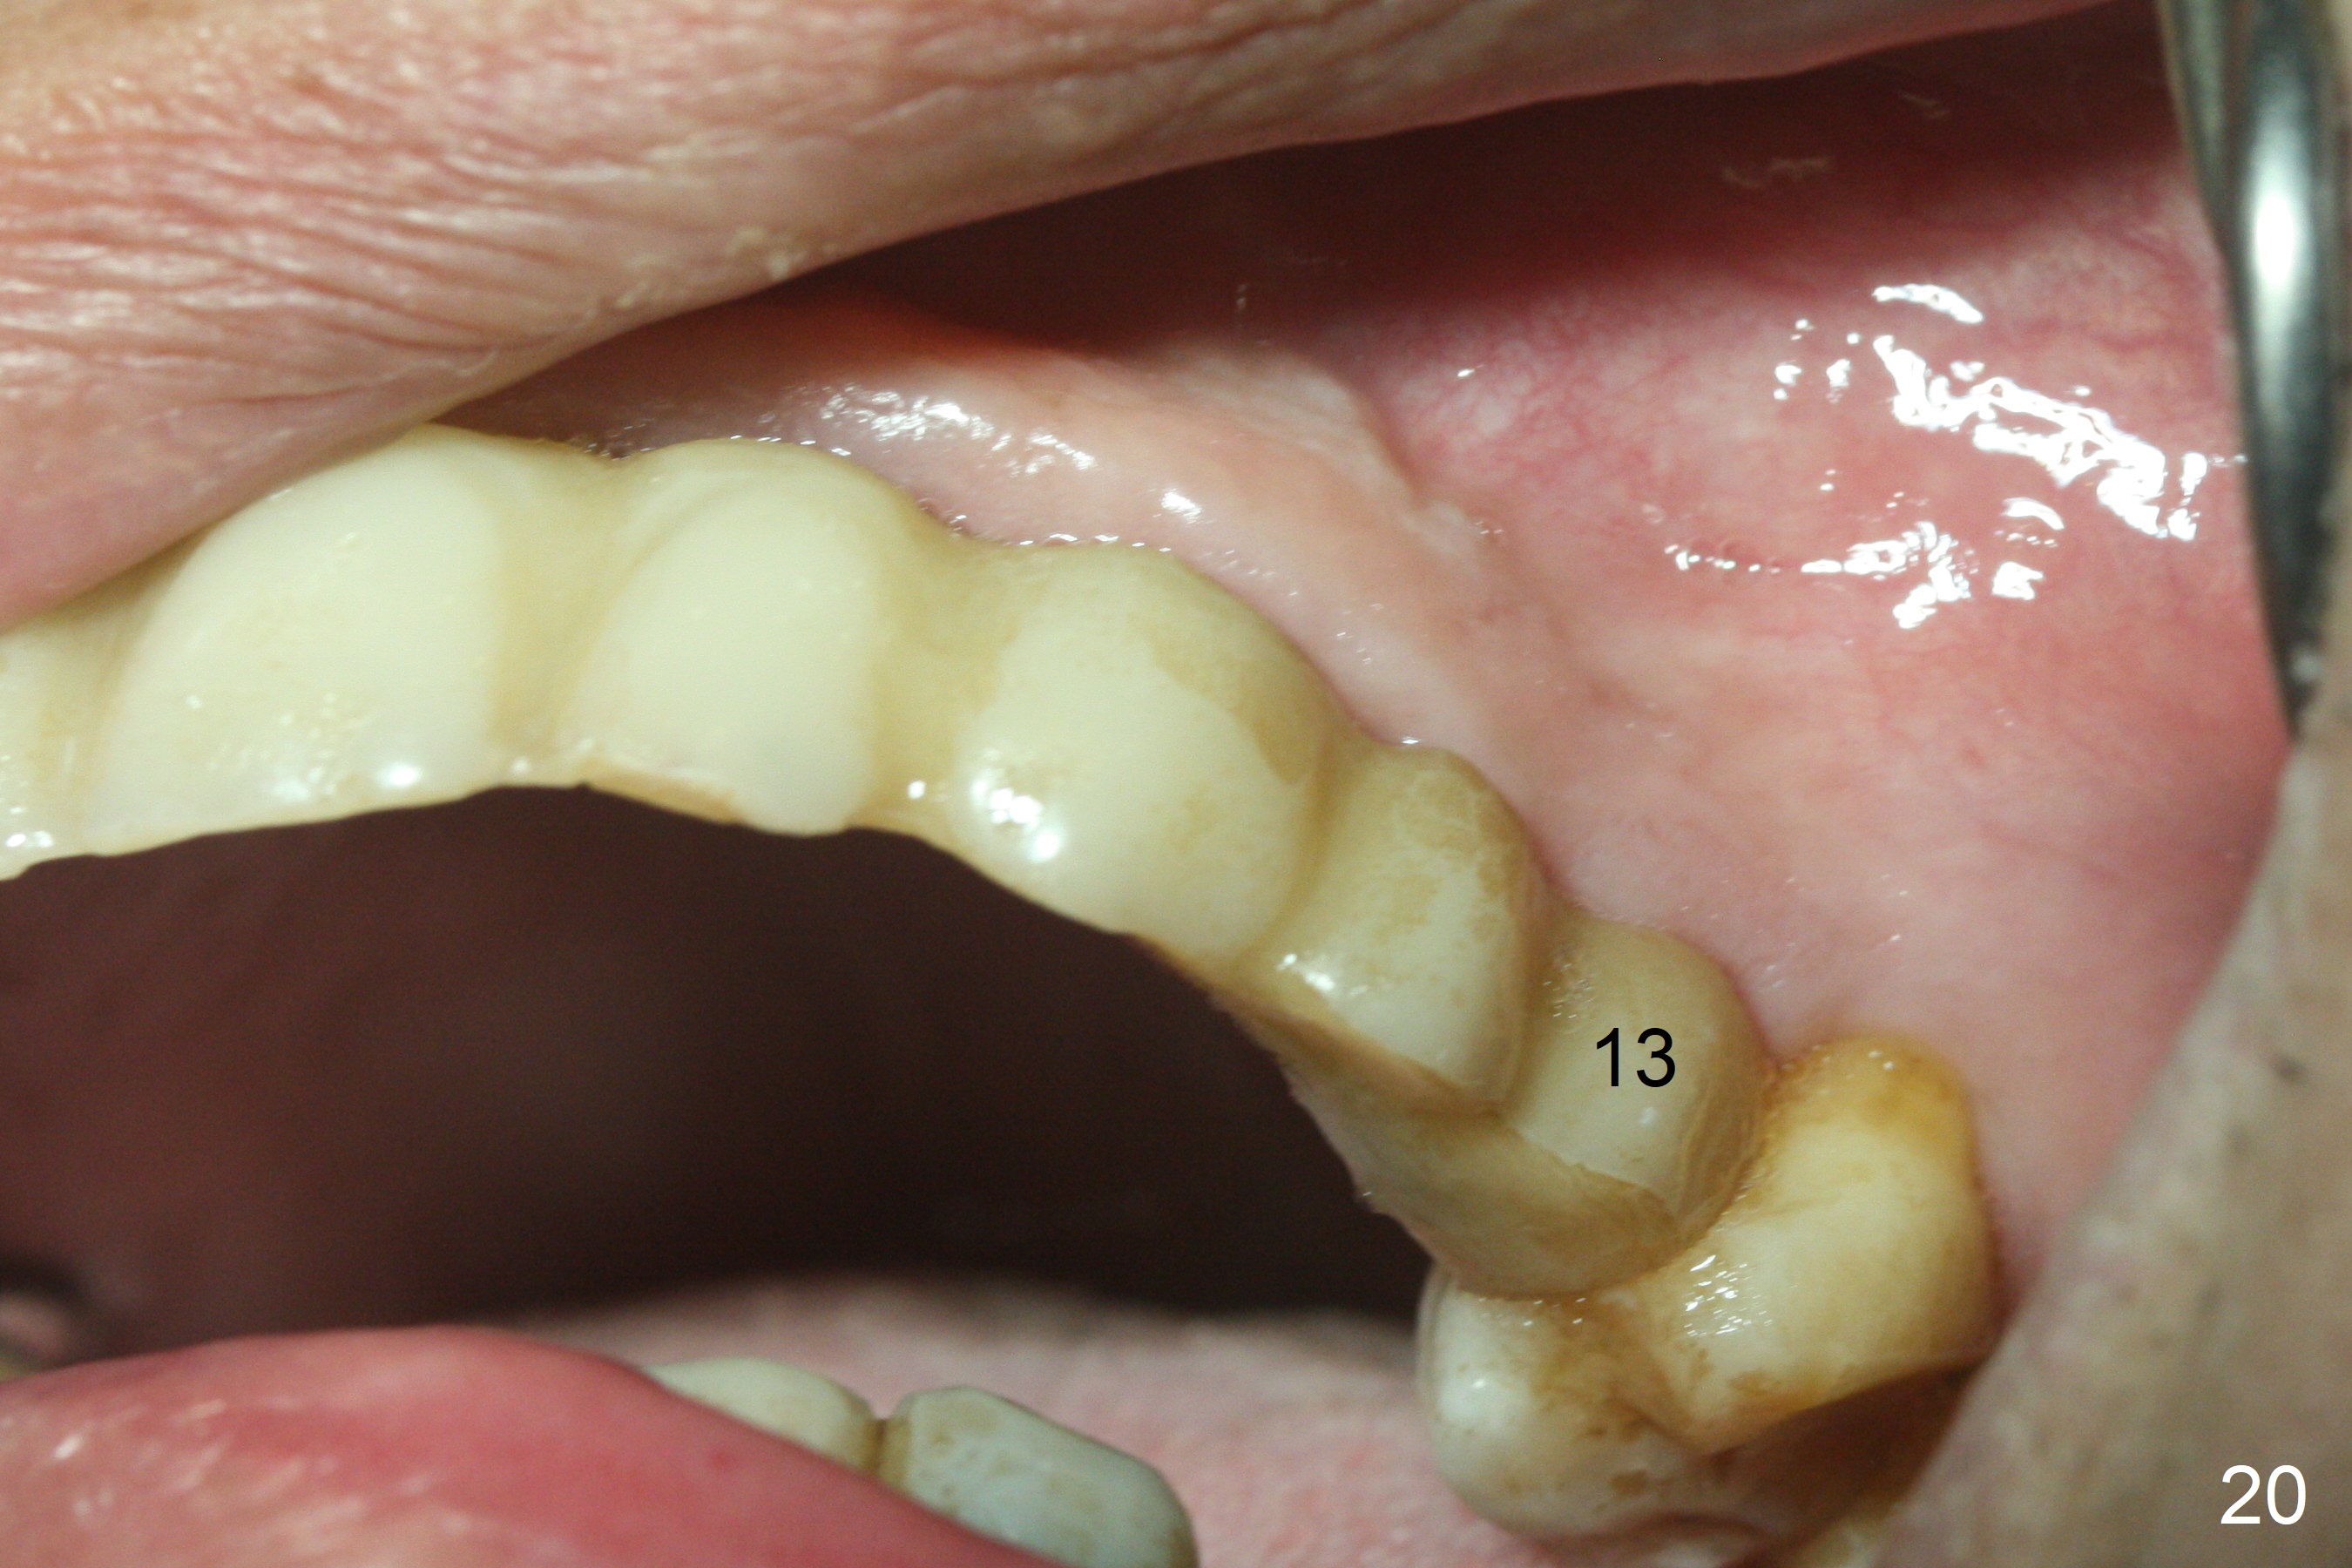

The soft tissue heals 2 weeks postop (Fig.20).